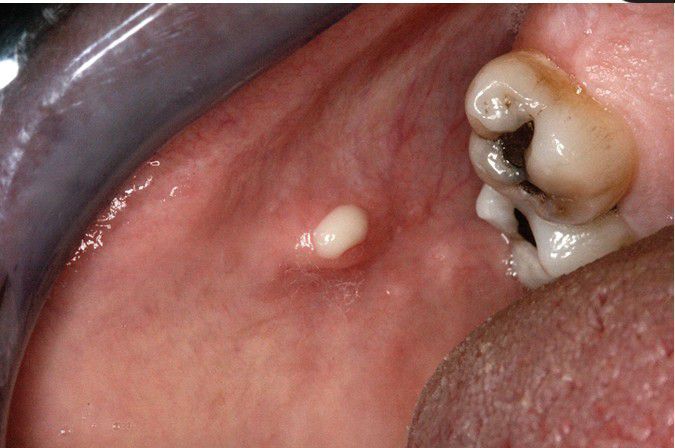

Sialadenitis

. A purulent exudate can be seen arising from Stensen duct when the parotid gland is massaged